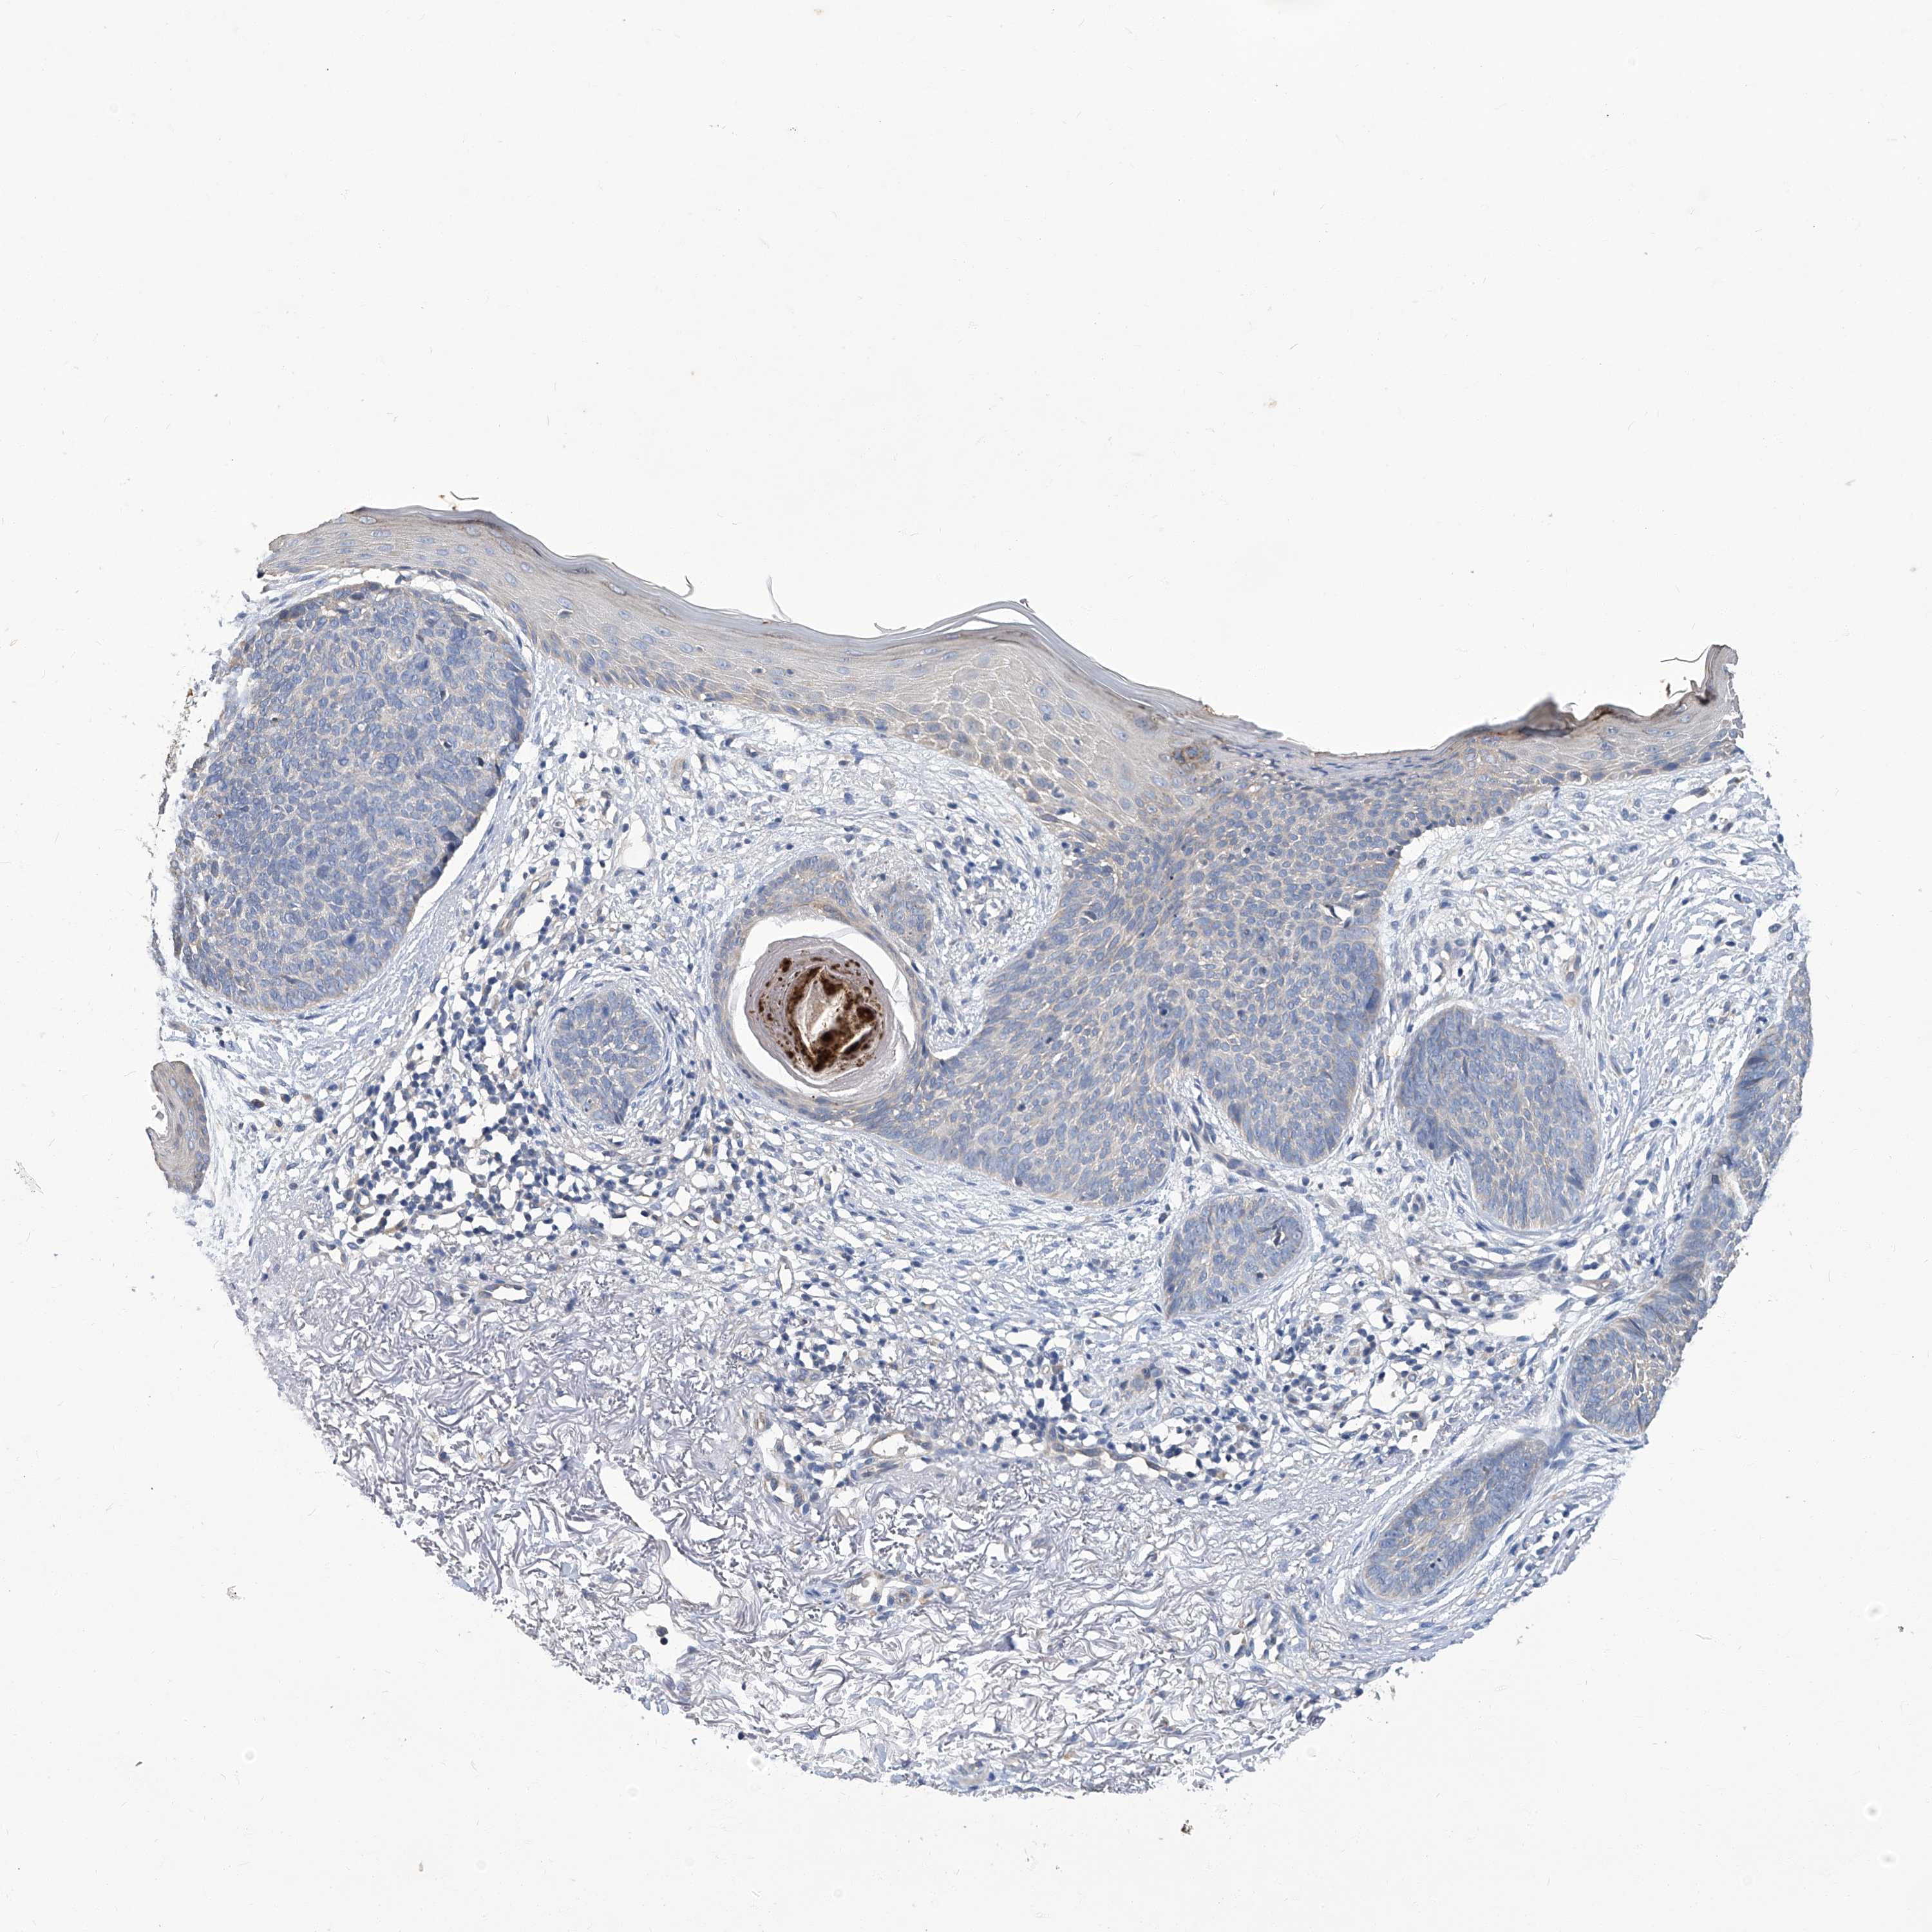

SKIN CANCER - Protein expressioni

A mouse-over function shows sample information and annotation data. Click on an image to view it in a full screen mode. Samples can be filtered based on level of antibody staining by selecting one or several of the following categories: high, medium, low and not detected. The assay and annotation is described here.

Each image is clickable and will lead to virtual microscopy that enables deeper exploration of all samples and also displays staining intensity scores, fraction scores and subcellular localization as well as patient and tissue information for each sample.

Antibody CAB031481

Basal cell carcinoma